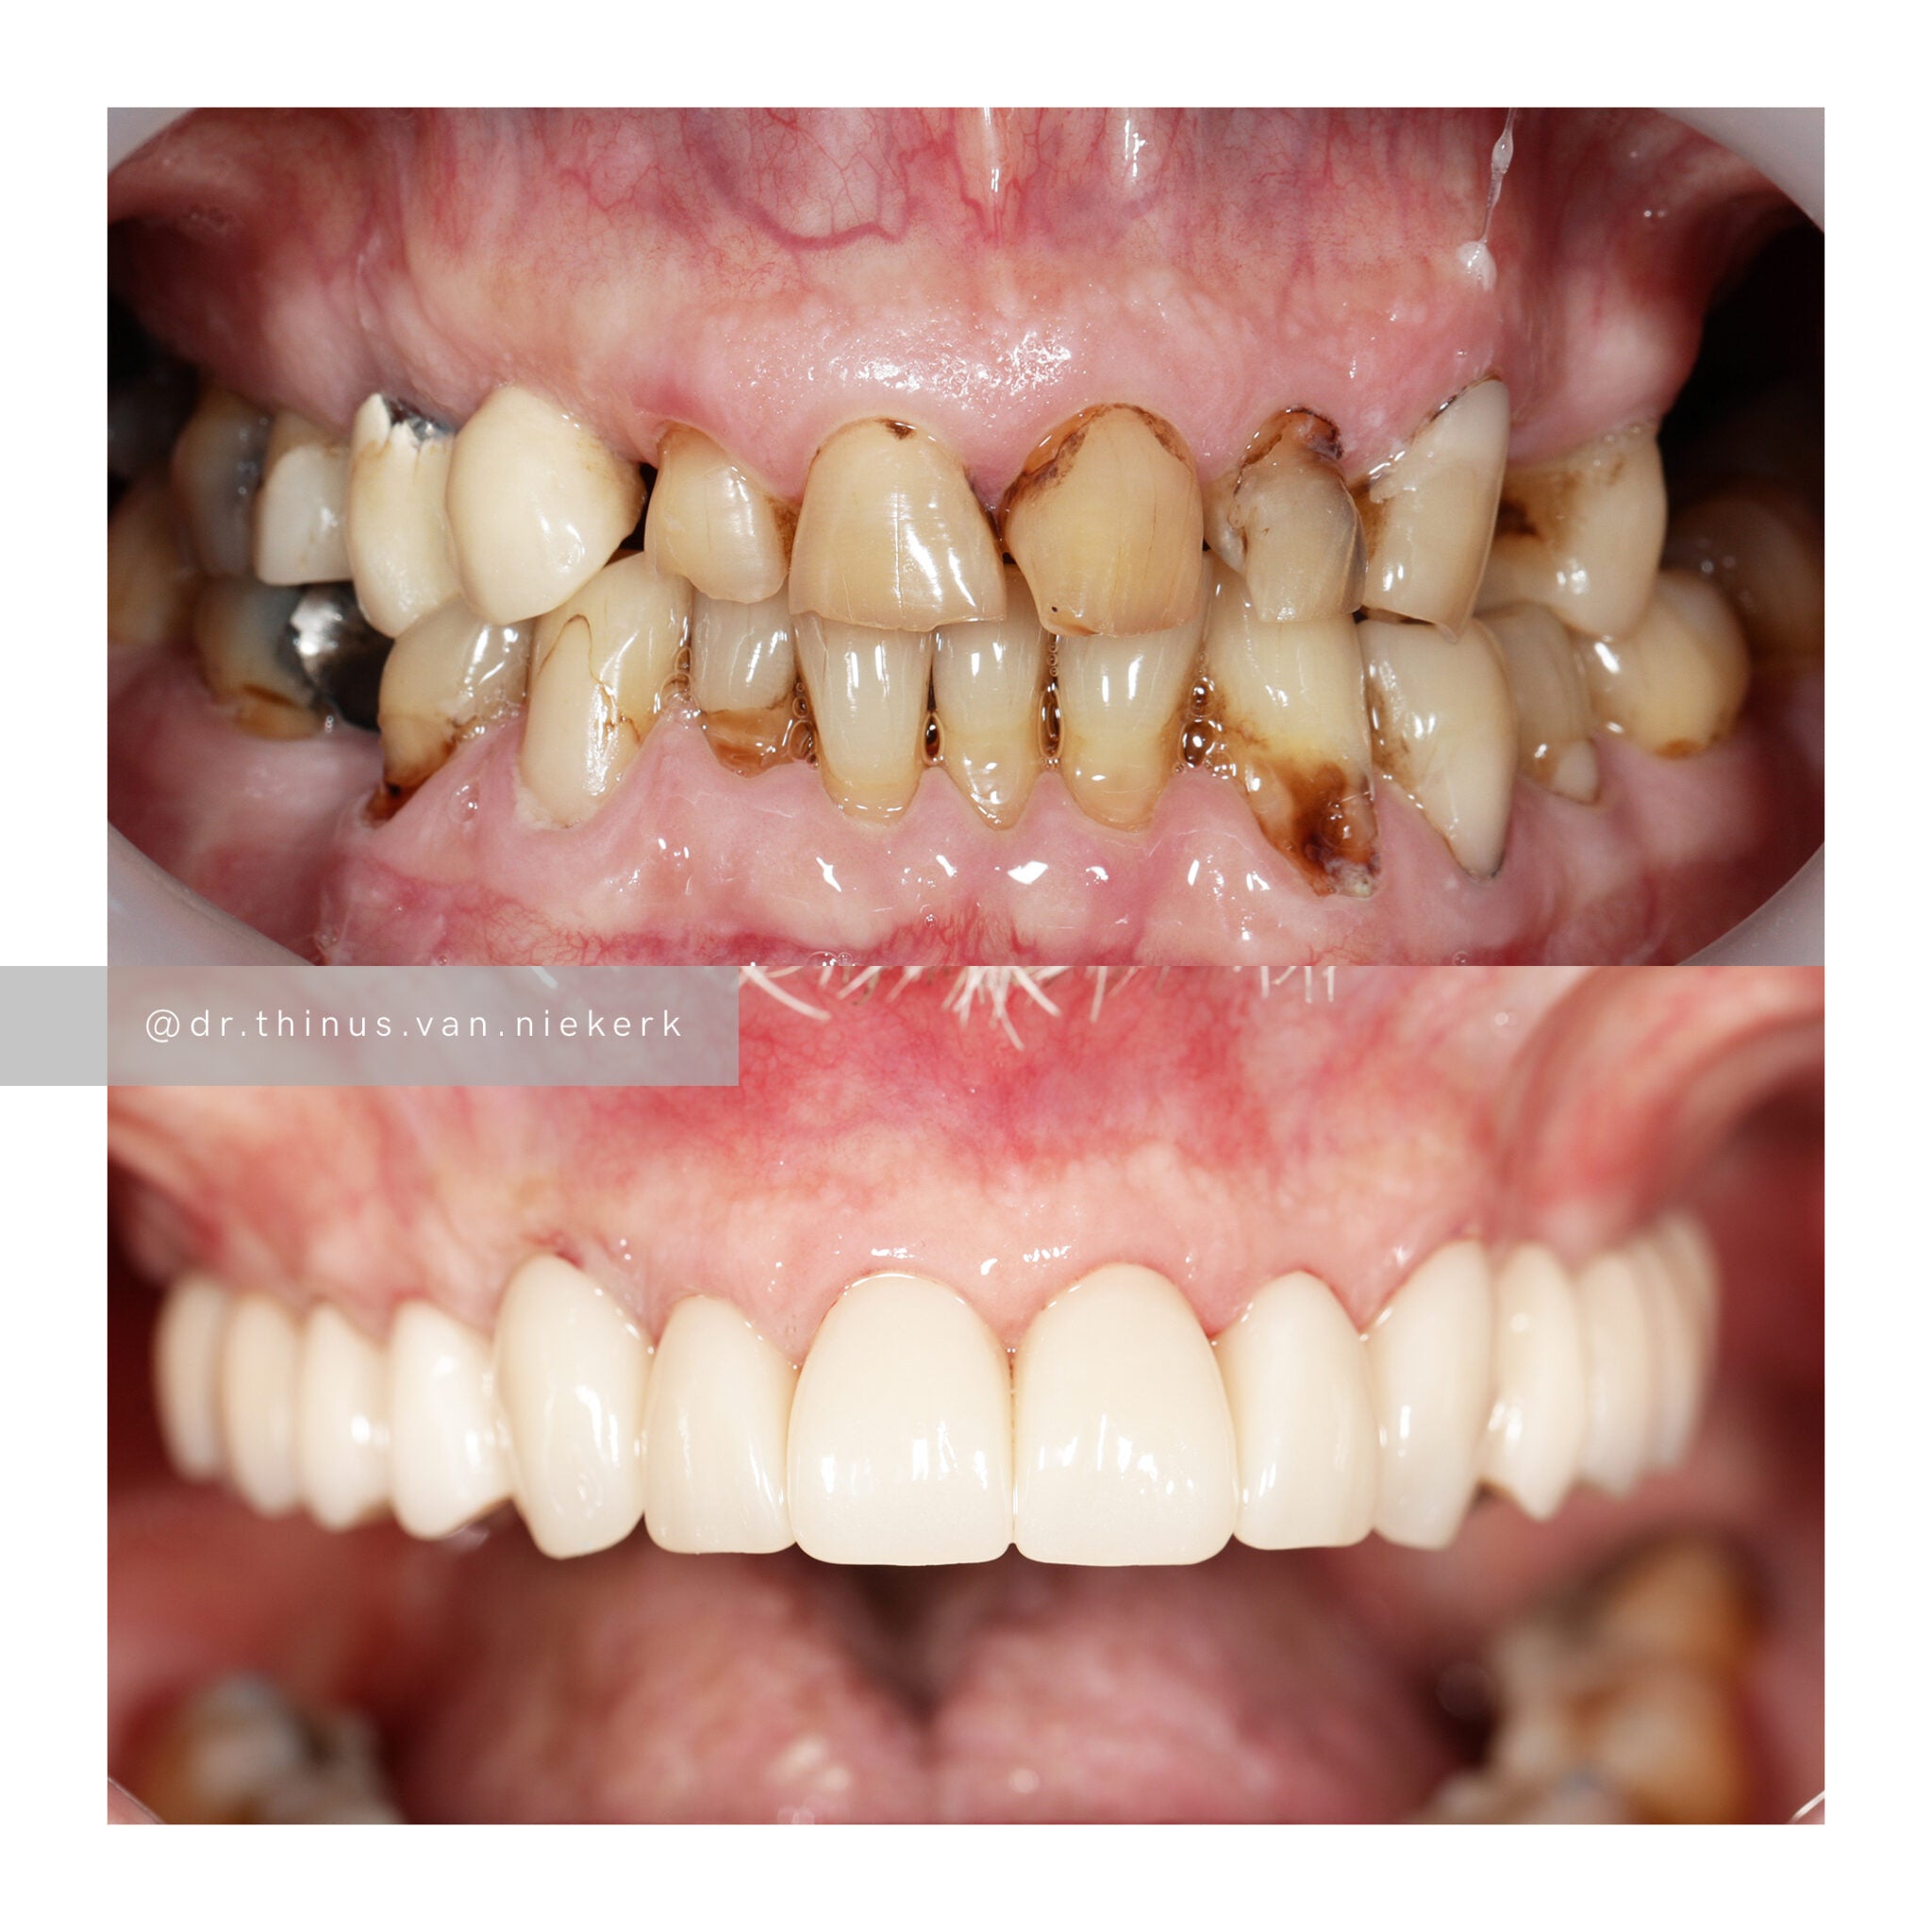

Case 3

TREATMENT OBJECTIVE

Our aim was to remove all elements of infection and disease and to restore function as quickly as possible. The complete case was digitally planned prior to the day of surgery. Six fully-guided implants were placed during a two-hour morning surgery. An immediate implant-supported prosthesis was delivered on the same day.

COMMENTS

This case demonstrated the power and effectiveness of digital implant-surgery planning and CAD design software.